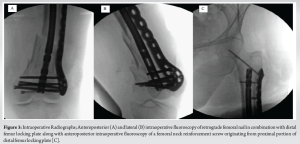

The patient was a 99-year-old female, a community ambulator with a cane, who presented after a fall from a standing height. Her past medical history was notable for hypertension, hyperlipidemia, chronic kidney disease stage 3A, and anemia. There was an obvious deformity of the left thigh as well as a punctate wound over the anterior distal thigh measuring two centimeters. She had a normal distal neurovascular examination. Plain radiographic images were obtained of her left femur and knee demonstrating a comminuted supracondylar distal femur fracture with a sagittal intercondylar split (OTA classification 33A3.3) (Fig. 1a and b). A CT scan of her knee was obtained confirming her radiographic findings (Fig. 2a-c) and air around the fracture site.

The patient was indicated for operative repair of the intra-articular and femoral shaft components. She received standard open fracture antibiotic prophylaxis for a Type 1 open distal femur fracture which included 2 g intravenous Cefazolin. Pre-operative protocols were undertaken and informed consent was obtained. Standard perioperative antibiotics were administered, and sterile prepping and draping were performed. The open fracture site was first extended into an anterolateral approach to the distal femur to allow for proper visualization of the zone of injury, and the open fracture was irrigated and debrided. Attention was first turned to the intra-articular component where two cannulated 5.0 mm screws were placed percutaneously from medial to lateral to compress the fracture line. Next, the femoral shaft component was addressed and a retrograde nail was inserted across the fracture. The decision was then made to further stabilize the intra-articular distal component via additional plate and screw fixation. Through the anterolateral incision, a distal femur locking plate was applied to the bone and a series of locking screws were placed proximally and distally (Fig. 3a and b).